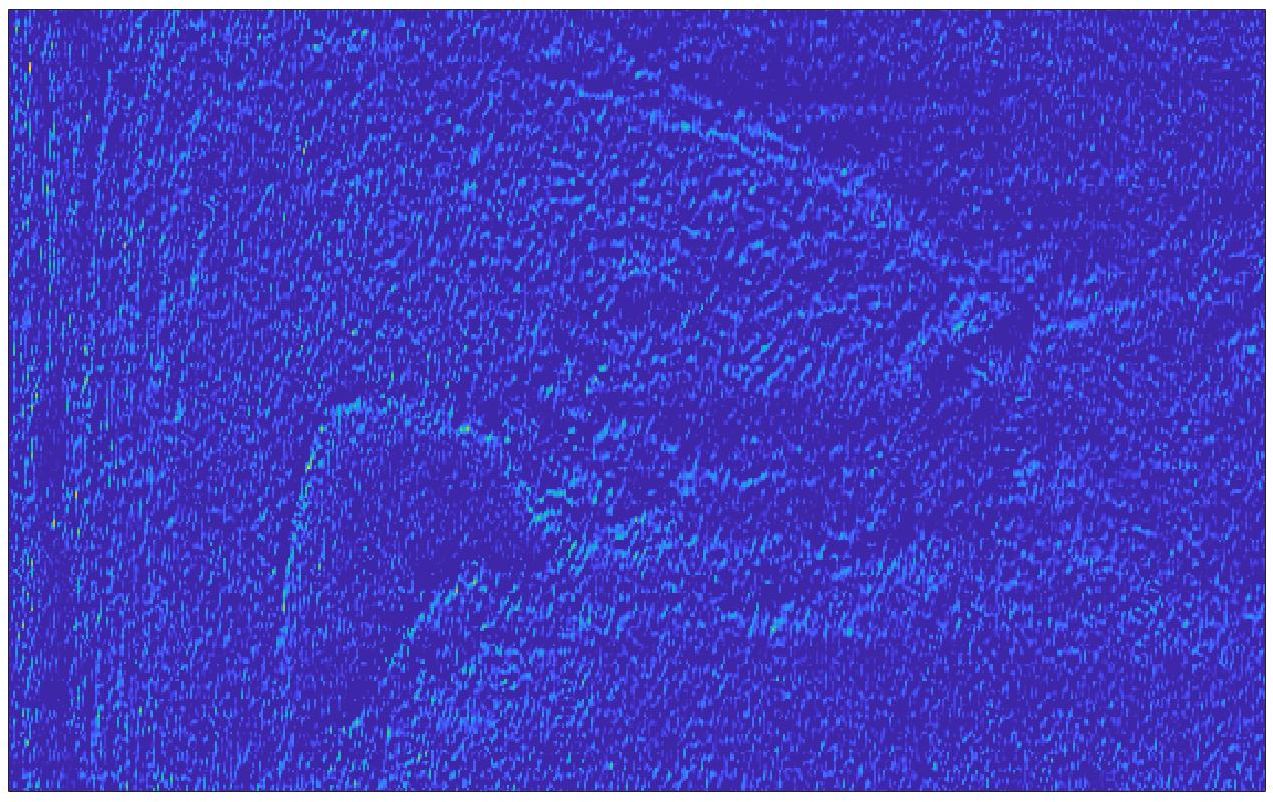

We train each learning-based network (custom-WDSR) with 1.5K images, where the input is the outcome of the selected up-sampling method (i.e., Cubic convolution), and the target is the original high-resolution image. Indeed, input and target images have the same resolution, as the reconstruction of the missing lines has been already performed by Cubic convolution. Figs. 3, 4, and 5 show the results of the network prediction, compared with the input and the target images. Target images correspond to spatial high-resolution images; input images are the outcome of the up-sampling interpolation, which is applied to spatial low-resolution images (i.e., the down-sampling along the lateral direction of high-resolution images); prediction images represent the output of the neural network.

Our framework visually improves the results, in terms of blurring and artefacts. This result is more evident in the magnification of the ear of the foetus (Fig. 3), the mitral valve (Fig. 4), and the mass edges (Fig. 5). Fig. 6 shows the error image of the three anatomical districts with both 2X and 4X up-sampling factors, with the maximum error in the scale . The error is more evident in the contours of the anatomical structures; moreover, the abdominal district shows a smaller error than the cardiac and obstetric ones. We underline that the view for each image is scaled to its maximum, to improve the visualisation of the error.